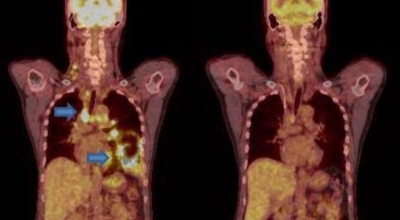

폐암 4기 생존율

폐암은 3기 이상인 말기에 발견되는 경우가 대개라 예전에는 폐암 판정을 받으면 곧 사망이라고 하는 말까지 있답니다. 하지만 요즘엔 의료기술이 발달하여 폐암 5년 생존율은 70%가 넘고 있답니다. 무엇보다 주기적인 건강검진으로 인해서 폐암을 조기에 발견한 경우가 많아서라고 볼 수 있어요. 세세히 살펴보면 인산화효소 변이 폐암 환자의 경우 5년, 상피세포 성장인자 수용체 변이 폐암 환자의 경우 1년~3년의 생존율을 보인다고 해요. 하지만 요즘도 폐암을 3~4기에서 확진 받는 경우가 많아요.

폐암 치료방법

폐암 검사는 X-ray를 통해서 검사하는데 , 크기가 작거나 구석에 위치한 경우 확인이 어려운 경우도 있습니다. 그리고 조직 검사를 통해서 정확한 진단을 하게 돼요. 폐암이 발견되면 종양의 크기나 전이 여부 , 위치에 따라서 수술 여부를 결정하게 되어요.